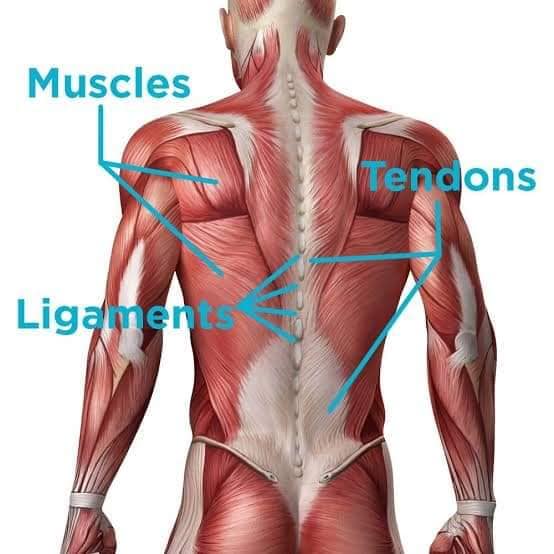

Скелетні м'язи з'єднані з кістками за допомогою сухожиль і відповідають за більшість волевих рухів. Вони поділяються на:

Спинні м'язи

Спинні м'язи виконують функції підтримки хребта, а також дозволяють здійснювати рухи тулуба.

Поверхневі спинні м'язи

М'язи, що піднімають лопатку: Трапецієподібний м'яз: великий м'яз, що покриває верхню частину спини. Його функція - підтримка і рух лопаток, а також забезпечення стабільності хребта.

М'язи, що ведуть лопатку до хребта: Широкий м'яз спини: великий м'яз, що розташований в нижній частині спини. Він відповідає за рухи плечей і лопаток, а також за розширення верхньої частини тулуба.

Глибинні спинні м'язи

М'язи, що забезпечують стабільність хребта: М'язи, що розташовані між хребцями: включають мускулатуру, яка забезпечує стабільність і підтримку хребта, а також дозволяє здійснювати рухи хребта.